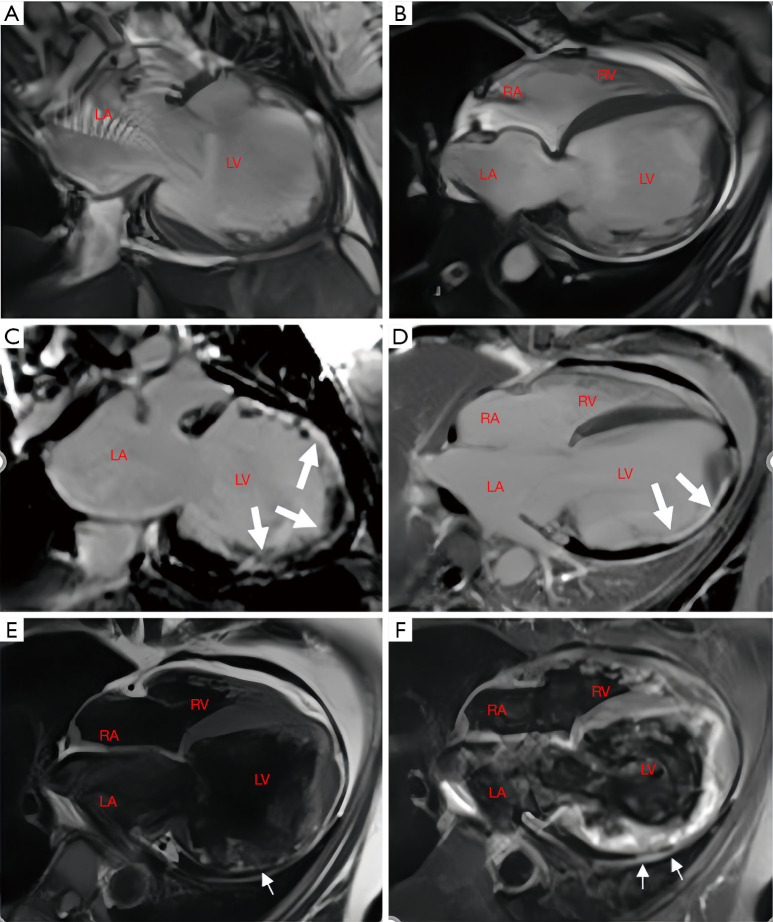

Case description: In this report, we describe a case of secondary syncope in a patient with ALVC who developed right bundle branch block with ventricular tachycardia (RBBB-VT), with VT originating in the left ventricle (LV). Cardiac magnetic resonance (CMR) revealed significant enlargement of the LV, with LV dysfunction. Late gadolinium enhancement (LGE) and fat sequencing revealed that most of the free wall of the LV was replaced by fibrofatty tissue.